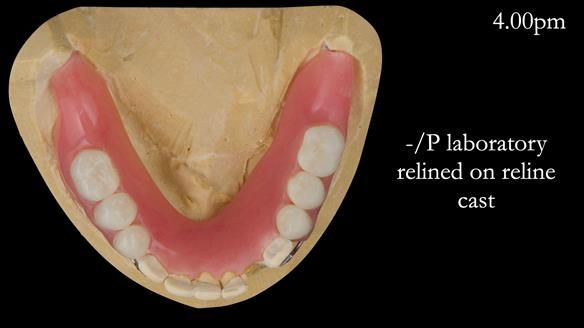

This newsletter describes the full protocol workflow of a complete upper denture and a lower partial denture for Jo.

The clinical situation and treatment process is shown in detail below. I provided the clinical work. Rowan Garstang provided the technical work. This treatment took 25 visits over a period of 12 months.